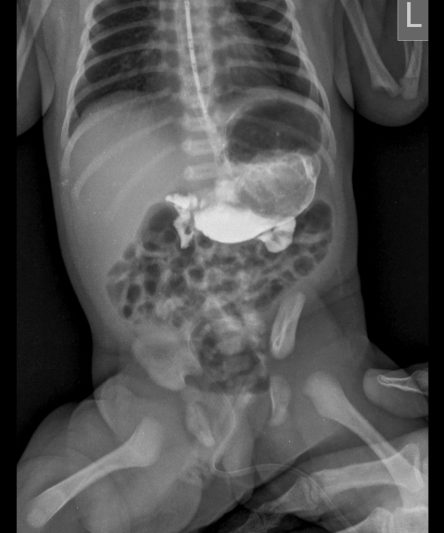

Microskan with Ultra high frequency can take the Lateral Lumbar Spine image of a 90 kg Patient with the correct image receptor